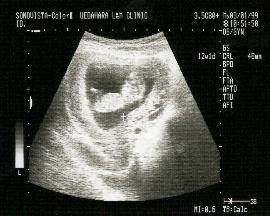

10ヶ月になると写真のように

2600グラム〜3400グラムの間になります

さあ、もうすぐ赤ちゃんに会えますね。